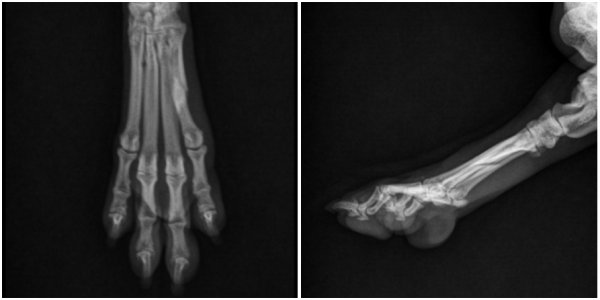

영상 검사(X-ray)를 통한 정밀 진단

정확한 병변 위치와 골절 형태를 확인하기 위해

방사선(X-ray) 검사를 시행하였습니다.

→ 영상 검사 결과

좌측 후지 5번째 발허리뼈에서

골절선이 명확히 확인되었으며, 골절 부위의 안정성이 떨어져

보존적 치료만으로는 회복이 어렵다고 판단하였습니다.